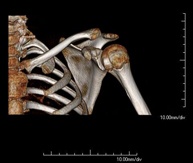

- Osteoarticular- TC Hombro Exploración radiológica que mediante un sistema de rayos X y detectores que giran alrededor del paciente, reconstruyendo las imágenes por ordenador (TC Multidetector), permite el estudio de huesos, músculos y articulaciones del hombro. Exploración radiológica que mediante un sistema de rayos X y detectores que giran alrededor del paciente, reconstruyendo las imágenes por ordenador (TC Multidetector), permite el estudio de huesos, músculos y articulaciones del hombro.